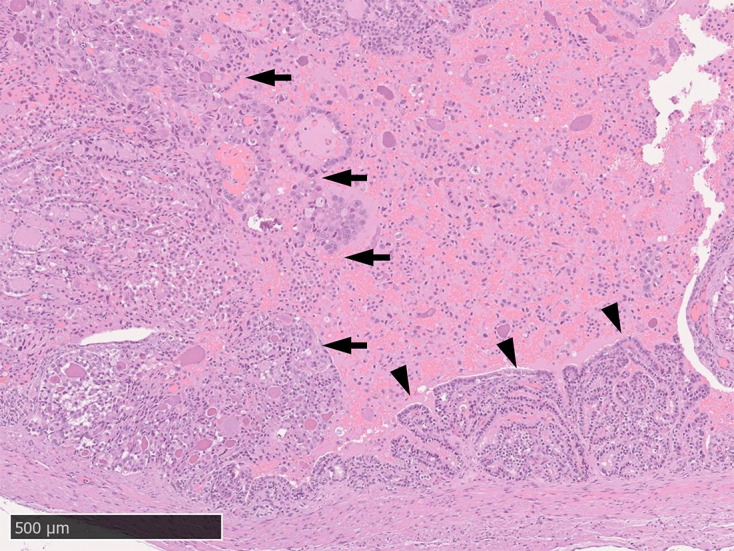

本文报告一例22岁雄性松鼠猴患原发性精囊腺癌(PSVA)。动物表现为血尿和消瘦。精囊肿瘤的病理解剖显示一个形状不规则的白色实性肿块,显示导管/乳头状和实性形态,导管内有周期性的酸-希夫阳性粘液。小泡因血液而扩张。肿瘤细胞呈细胞质嗜酸性颗粒,向肿瘤组织过渡。免疫组化分析显示所有肿瘤细胞角蛋白均为阴性;只有导管/乳头状细胞呈vimentin阳性。其他器官无肿瘤。PSVA的诊断基于肿瘤起源部位和组织病理学,类似于实验室啮齿动物的PSVA。本研究报告了一例新世界猴的PSVA。

This report presents the case of a 22-year-old male squirrel monkey with primary seminal vesicle adenocarcinoma (PSVA). The animal presented with hematuria and emaciation. Pathological autopsy of the seminal vesicle tumor revealed an irregularly shaped, white, solid mass showing ductal/papillary and solid patterns and periodic acid-Schiff-positive mucus in the duct. The vesicle was dilated by blood. Tumor cells showed cytoplasmic eosinophilic granules, and a transition to tumor tissue was observed. Immunohistochemical analysis indicated that all tumor cells were cytokeratin-negative; only ductal/papillary cells were vimentin-positive. Other organs were tumor free. PSVA was diagnosed based on the site of tumor origin and histopathology, similar to PSVA in laboratory rodents. This study reports a case of PSVA in a new-world monkey.